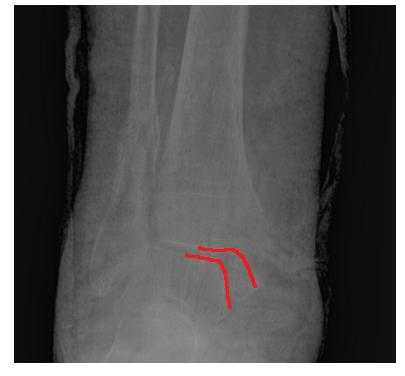

На рентгенограммах в гипсе определяется значительный подвывих таранной кости кнаружи, консолидирующийся перелом нижней трети малоберцовой кости.

В день обращения пациентка послоностью обследована, проведено оперативное лечение, открытая репозиция, остеосинтез перелома нижней трети малоберцовой кости пластиной, внутренней лодыжки винтом, внутренняя лодыжка дополнительно фиксирована анкерным фиксатором.

На контрольных рентгенограммах после операции положение отломков, металлофиксаторов правильное, подвывих таранной кости устранён.

Пациентка выписана на 2 сутки после операции на амбулаторное долечивание.